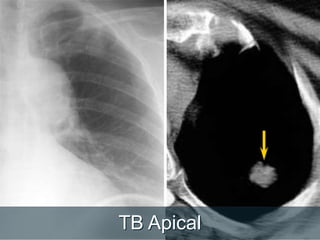

TB Apical

Nódulo Atrás do Diafragma

Faça uma segundaolhada  Ápices  Áreas retrocardiaca (esquerda e direita)  Regiões hilares  Região abaixo do diafragma